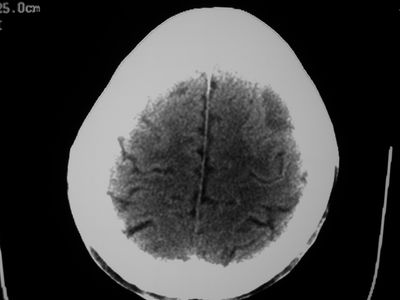

以下是引用卜一在2007-1-19 15:29:00的发言:[br]治疗前:1月14日右侧额叶皮质下低密度影,而治疗后:1月18日右侧阴影消失,新近出现左侧额叶侧脑室前角旁大片状低密度影,边缘模糊。支持—双侧额叶后部缺血性脑梗塞。